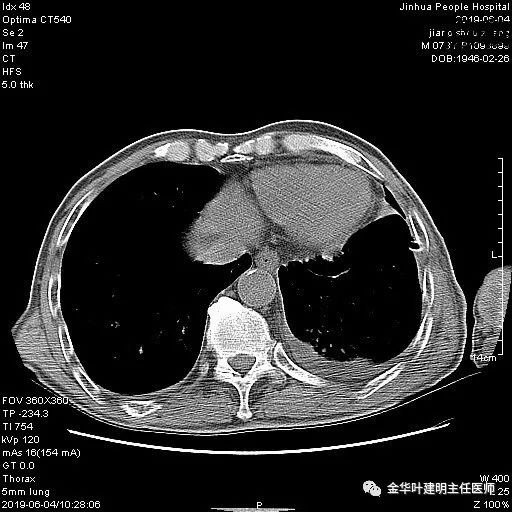

考虑左侧大量胸腔积液,遂进一步胸部CT检查:

以上是肺窗表现,下面为纵隔窗影像: